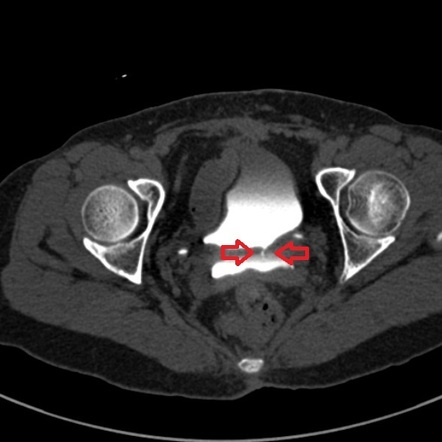

- CT KUB: if obstruction is suspected (to identify the site of obstruction

- CT KUB or IV pyelography or Cystoscopy or Retrograde pyelogram